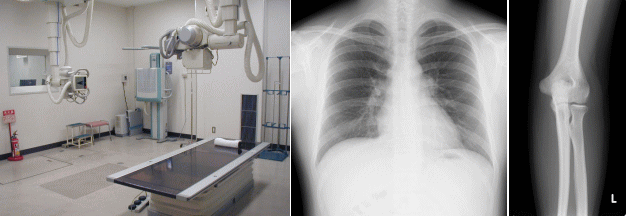

機器紹介(一般撮影)

俗にレントゲンと呼ばれるX線を用いた画像検査です。依頼に応じて、胸部や腹部、手や足など、様々な部位を撮影します。

撮影部位の近くに金属類や衣類のボタンなどがある場合、服を脱いで検査着に着替えてもらうことがあります。

入院患者さんなどで、撮影室への移動が困難な方には、移動式のポータブルX線装置を持っていって、病室で撮影することもできます。

一般撮影室

胸部レントゲン

肘部レントゲン